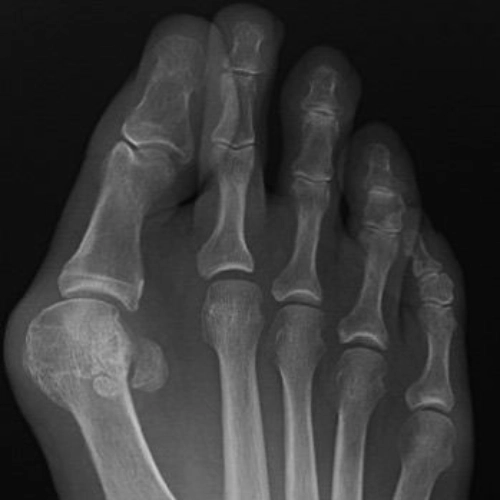

Bunion treatment to correct toe alignment and relieve foot painBunion treatment to correct toe alignment and relieve foot pain